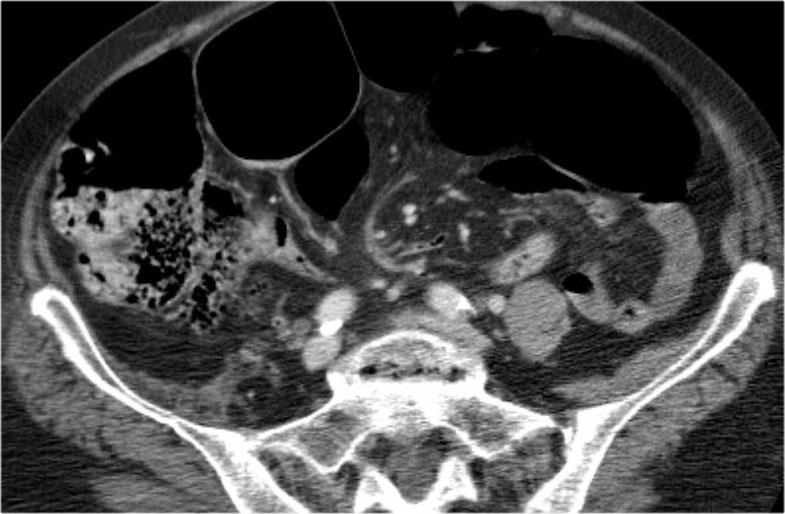

Đây là một trường hợp xoắn đại tràng sigma khác.

Trên X-quang bụng, rất khó nhận biết tình trạng bệnh lý vì có quá nhiều quai ruột giãn.

Tiếp tục với các hình ảnh CT.

Trên CT, chúng ta có thể thấy rõ vùng xoắn với đại tràng sigma kéo dài lên đến cơ hoành.

Đại tràng sigma là vị trí xoắn đại tràng thường gặp nhất.

Nó chiếm 75% các trường hợp tắc ruột già.